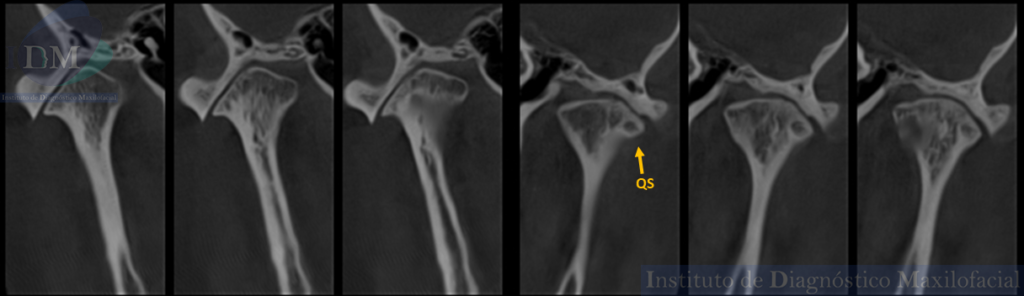

- Quiste óseo subcondral (QS), alteración en el hueso subcondral que refleja cambios degenerativos en la estructura ósea subyacente.

CORTES CORONALES